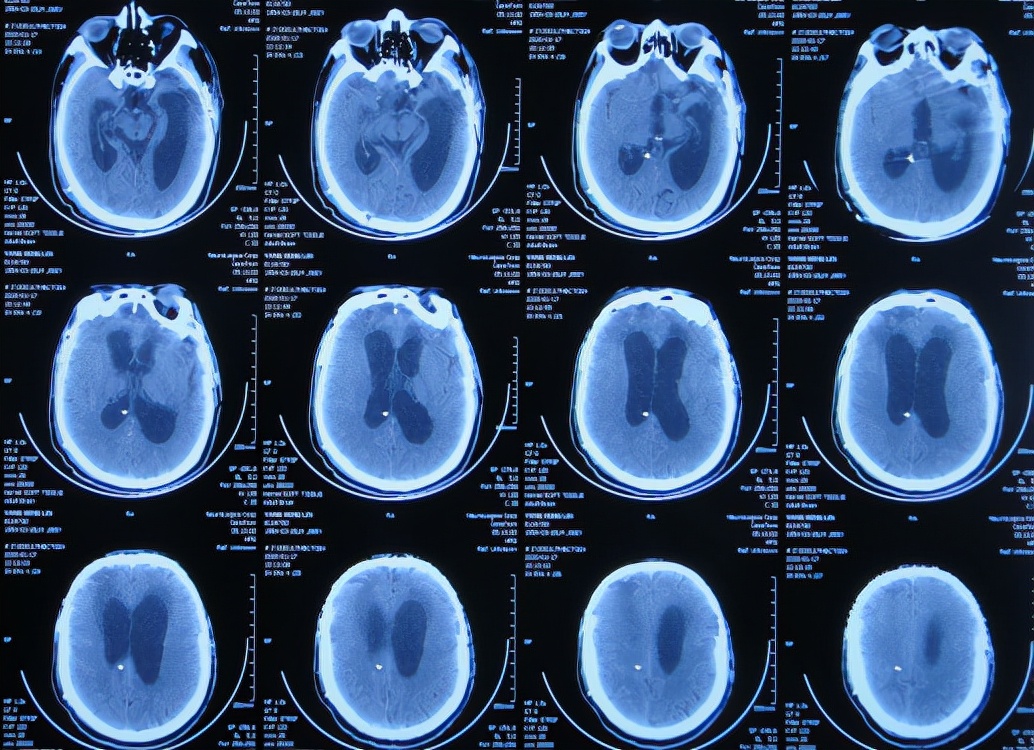

为求进一步有效治疗,于第1家医院出院后19天即2019年12月10日,住入第2家的北京某解放军的三甲医院,入院次日查头颅CT( 图-14 )后认为是脑积水。

图-14: 2019年12月11日头颅CT

入院3天即2019年12月13日,同时进行了颅骨修补术+脑室腹腔分流术。术后3天即2019年12月16日,在搀扶下可以下床走路活动,查头颅CT示颅骨修补术后+脑室引流术后状态( 图-15 )。

图-15: 2019年12月16日头颅CT

但颅骨修补术+脑室腹腔分流术后第5天即2019年12月18日,出现意识有点不清。

颅骨修补术+脑室腹腔分流术后第6天即2019年12月19日,复查头颅CT示引流管周围少量出血( 图-16 ),给予拔除头部引流,换做腰大池引流。

图-16: 2019年12月19日头颅CT

腰大池引流术后5天即2019年12月24日(颅骨修补术后11天即拔除脑室引流管后5天),查头颅CT示脑室仍扩张( 图-17 )。

图-17: 2019年12月24日头颅CT

腰大池引流术后8天即2019年12月27日(颅骨修补术后11天即拔除脑室引流管后8天),查头颅CT示脑室有缩小,积血减少( 图-18 )。

图-18: 2019年12月27日头颅CT

腰大池引流术后11天即2019年12月30日(颅骨修补术后11天即拔除脑室引流管后11天),查头颅CT示仍有脑室扩张( 图-19 )。

图-19: 2019年12月30日头颅CT

腰大池引流后13天即2020年1月1日,复查头颅CT( 图-20 )示认为积血基本吸收;给予拔除腰大池引流管。

图-20: 2020年1月1日头颅CT